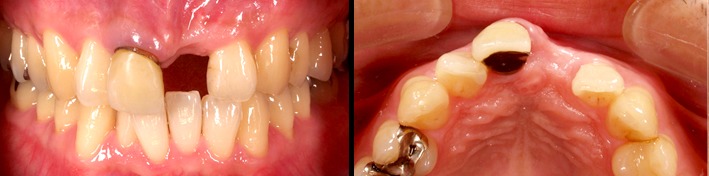

初診時

前歯を失った状態で時間が経過したため、骨が大きく吸収されています。